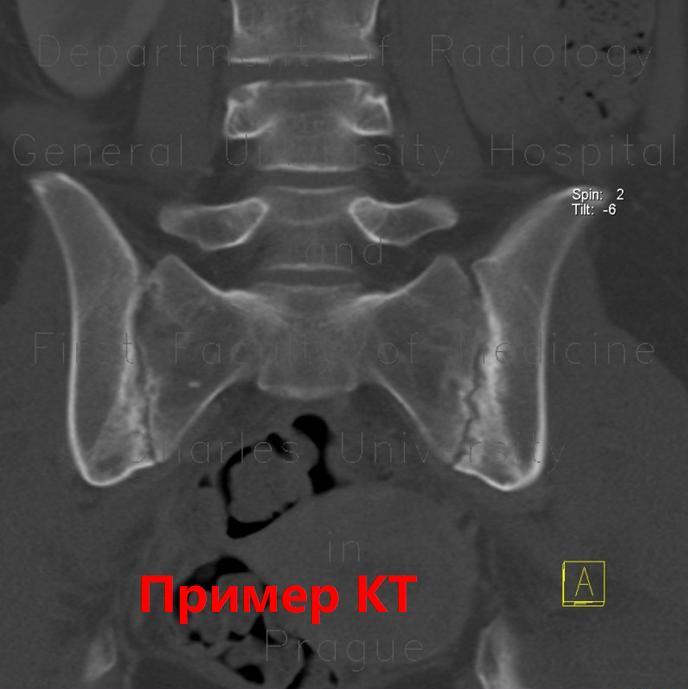

Примеры сакроилиита на КТ,МРТ: